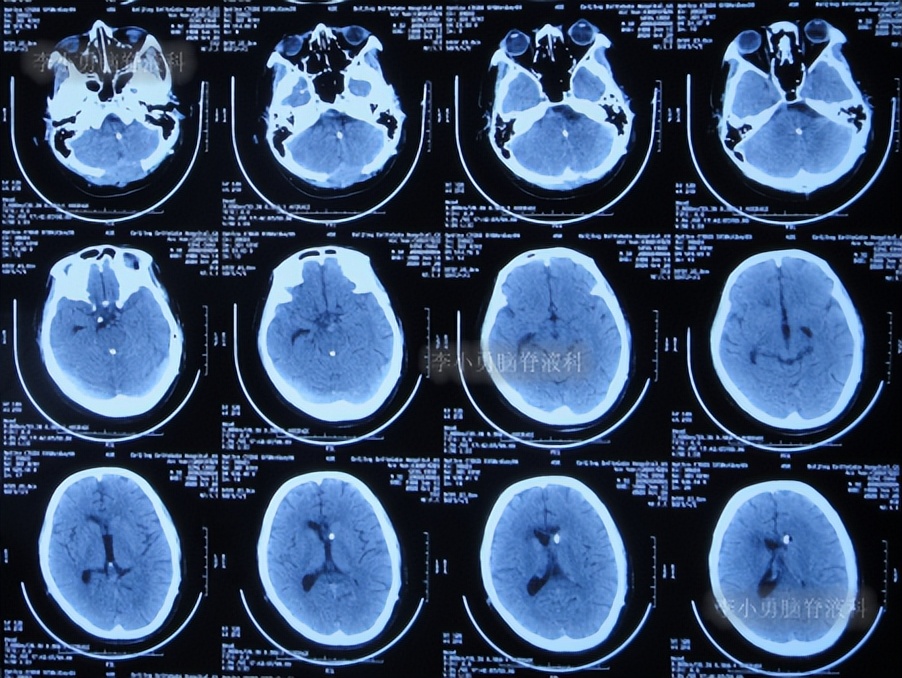

半月后即2022年6月17日,第3次住入李小勇脑脊液科,入院时:进食差,言语混乱,记忆力差,行走差(图-52);查头颅CT示右侧颞角增大,四脑室也稍大(图-53);肺部CT有感染(图-54)。

图-53:入院时头颅CT

2022年6月20日(入院后3天),进行了脑室腹壁外引流术,术前术后头颅CT对比(图-55)。

图-55:2022年6月20日术前术后头颅CT

2022年6月23日(入院治疗6天),查头颅CT示脑室周有水肿(图-56)。

图-56:2022年6月23 日头颅CT

2022年10月7日(入院治疗112天),查头颅CT示脑室周水肿消失,脑室变小(图-57)。

图-57:2022年10月7日头颅CT